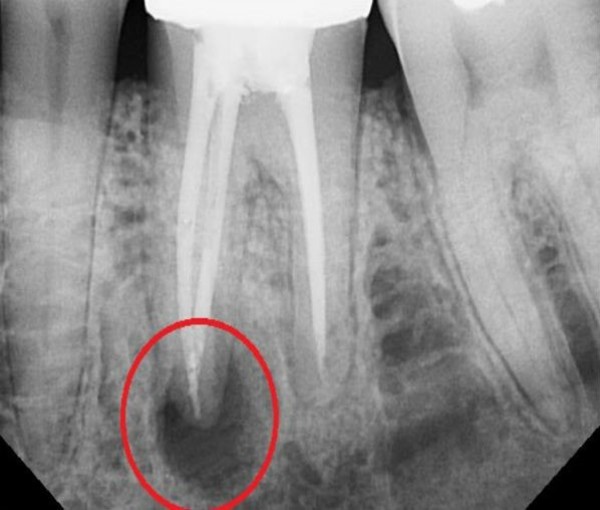

Одним из ведущих способов диагностирования болезни специалисты называют проведение рентгеновского обследования.

Фото 2. Рентгеновский снимок зуба при заболевании периодонтитом. Красным цветом выделена область воспаления.

Оно необходимо, чтобы выяснить состояние костной ткани челюсти, определить наличие кист или другого образования и есть ли возможность для сохранения зуба.

| Тип периодонтита | Признаки |

| Гранулёматозный | Наблюдаются очаговые патологические образования (гранулёмы), частичное разрежение кости, нечёткие контуры, затемнения, похожие на языки пламени. |

| Хронический | Значительное расширение периодонтальной щели. |

| Фиброзный | Рубцовая ткань в виде утолщения, выступы на корне зуба, затемнение зоны в верхней части корня зуба. |

| Маргинальный | Чётко просматриваются переломы, обломки инородных предметов, трещины. |